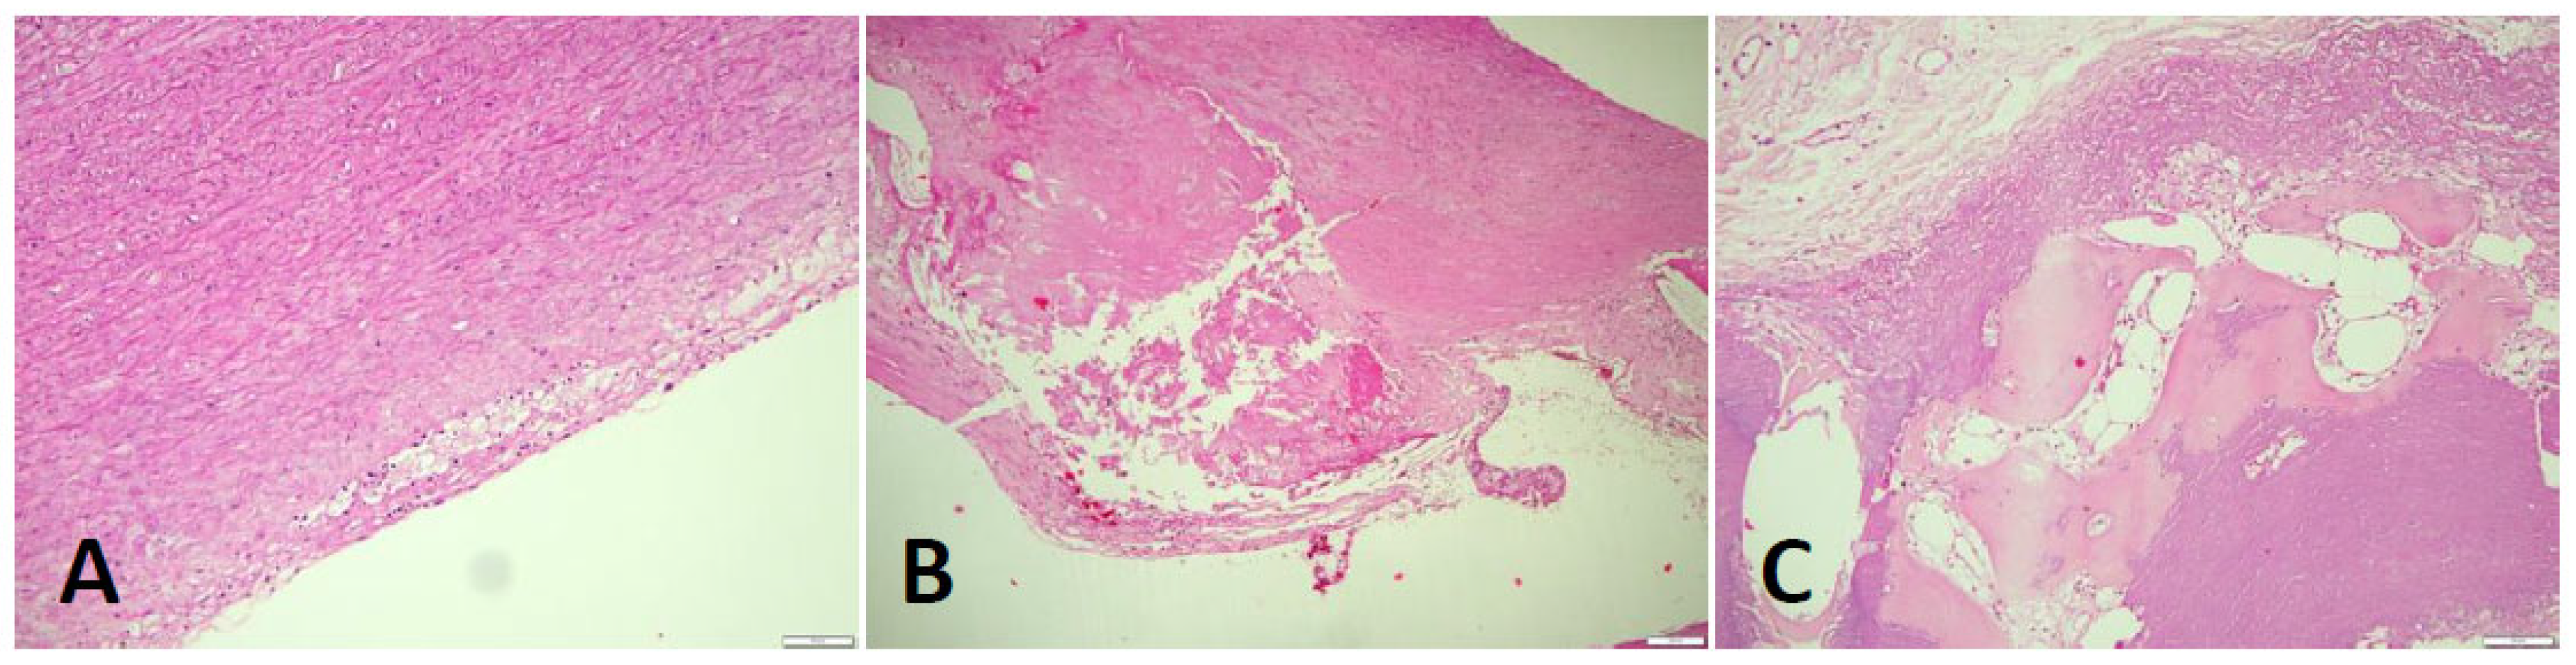

Figure 4.

Arteriosclerotic lesions in the aortic wall (HE stain): In the samples examined, the degree of atherosclerosis varied markedly from mild to severe cases. In the initial plaque, a few foam cells can be demarcated in the intimal layer (A), which may eventually appear macroscopically together with smooth muscle proliferates as so-called "fatty streaks". In the advanced atheromatous bed (B) smooth muscle proliferates are more prominent in the arterial wall. In addition, abundant cholesterol-containing material can be seen. In isolated cases, heterotopic ossification with formation of bone bellows and intervening medullary spaces was seen in the plaque (C).